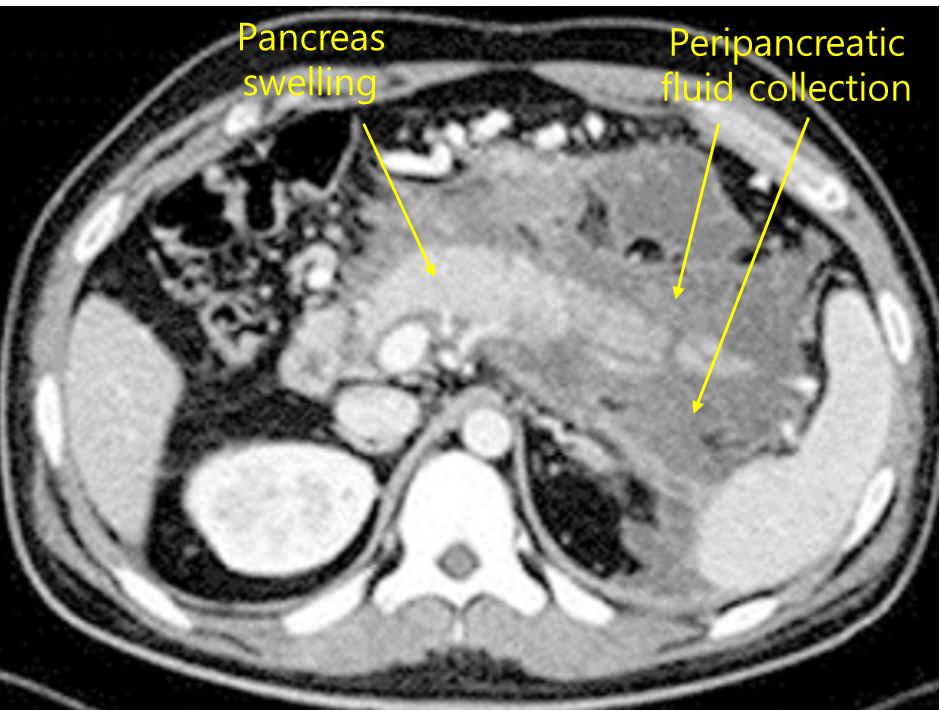

50세 남자가 배가 불러서 병원에 왔다. 최근 들어 매일 술을 마셨다고 한다. 혈압 100/65mmHg, 맥박 115회/분, 호흡 20회/분, 체온 36.5℃이다. 장음은 감소되어 있고 배 전체에 압통이 있고 반동압통은 없다. 혈액검사 결과는 다음과 같다. 복부 컴퓨터단층촬영 사진이다. 우선 금식 조치를 취하였다. 다음으로 시행해야 할 조치는?

혈색소 13.4g/dL, 백혈구 9,800/mm3, 혈소판 254,000/mm3, 총단백질 5.9g/dL, 알부민 2.7g/dL, 총빌리루빈 1.2mg/dL, 알칼리인산분해효소 165U/L, 아스파르테이트아미노전달효소 48U/L, 알라닌아미노전달효소 35U/L, 아밀라아제 5,100U/L, 리파제 1,500U/L, C-반응단백질 4mg/L(참고치, <10)

Img | CT: 이자 주위 염증, fluid collection |

최근의 잦은 음주력, lab 상 amylase, lipase의 심한 상승으로 급성 췌장염을 의심하고, 복부 CT 상 췌장 주위 액체 저류 소견으로 확진할 수 있다. 급성 췌장염의 1차 치료는 수액공급, 진통제 등 보존적 치료를 시행한다.

진단 | • US: 담석, 담관확장 확인 • CT: 췌장 실질의 edema, 췌장 근처 조직의 inflammation |